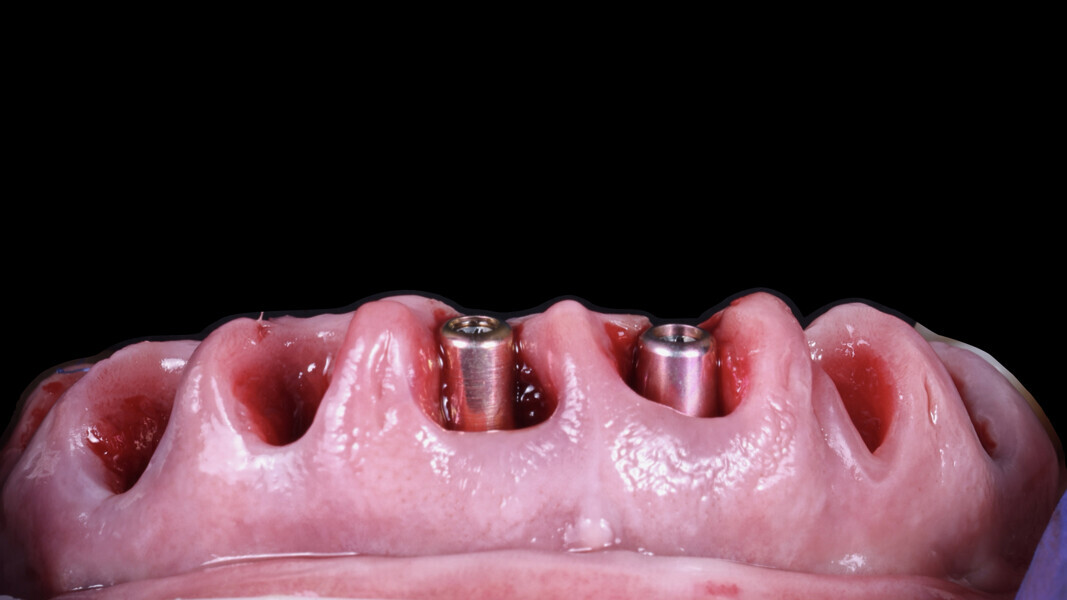

4. Guided implant placement: Eight implants were placed using a guided approach, achieving optimal progressive torque of 35 N cm and excellent bone–implant contact (Fig. 17).

5. Multi-unit abutment seating: The multi-unit abutments were torqued to 25 N cm.

6. Placement of SmartFlag scan bodies: The scan bodies were attached. The remaining teeth served as reference points for the dental technician to align the digital impression with the preplanned design and fabricate the temporary restoration.

7. Final tooth extractions: The remaining teeth were extracted to ensure a clean surgical site, and healing abutments were placed on the implants (Fig. 18).